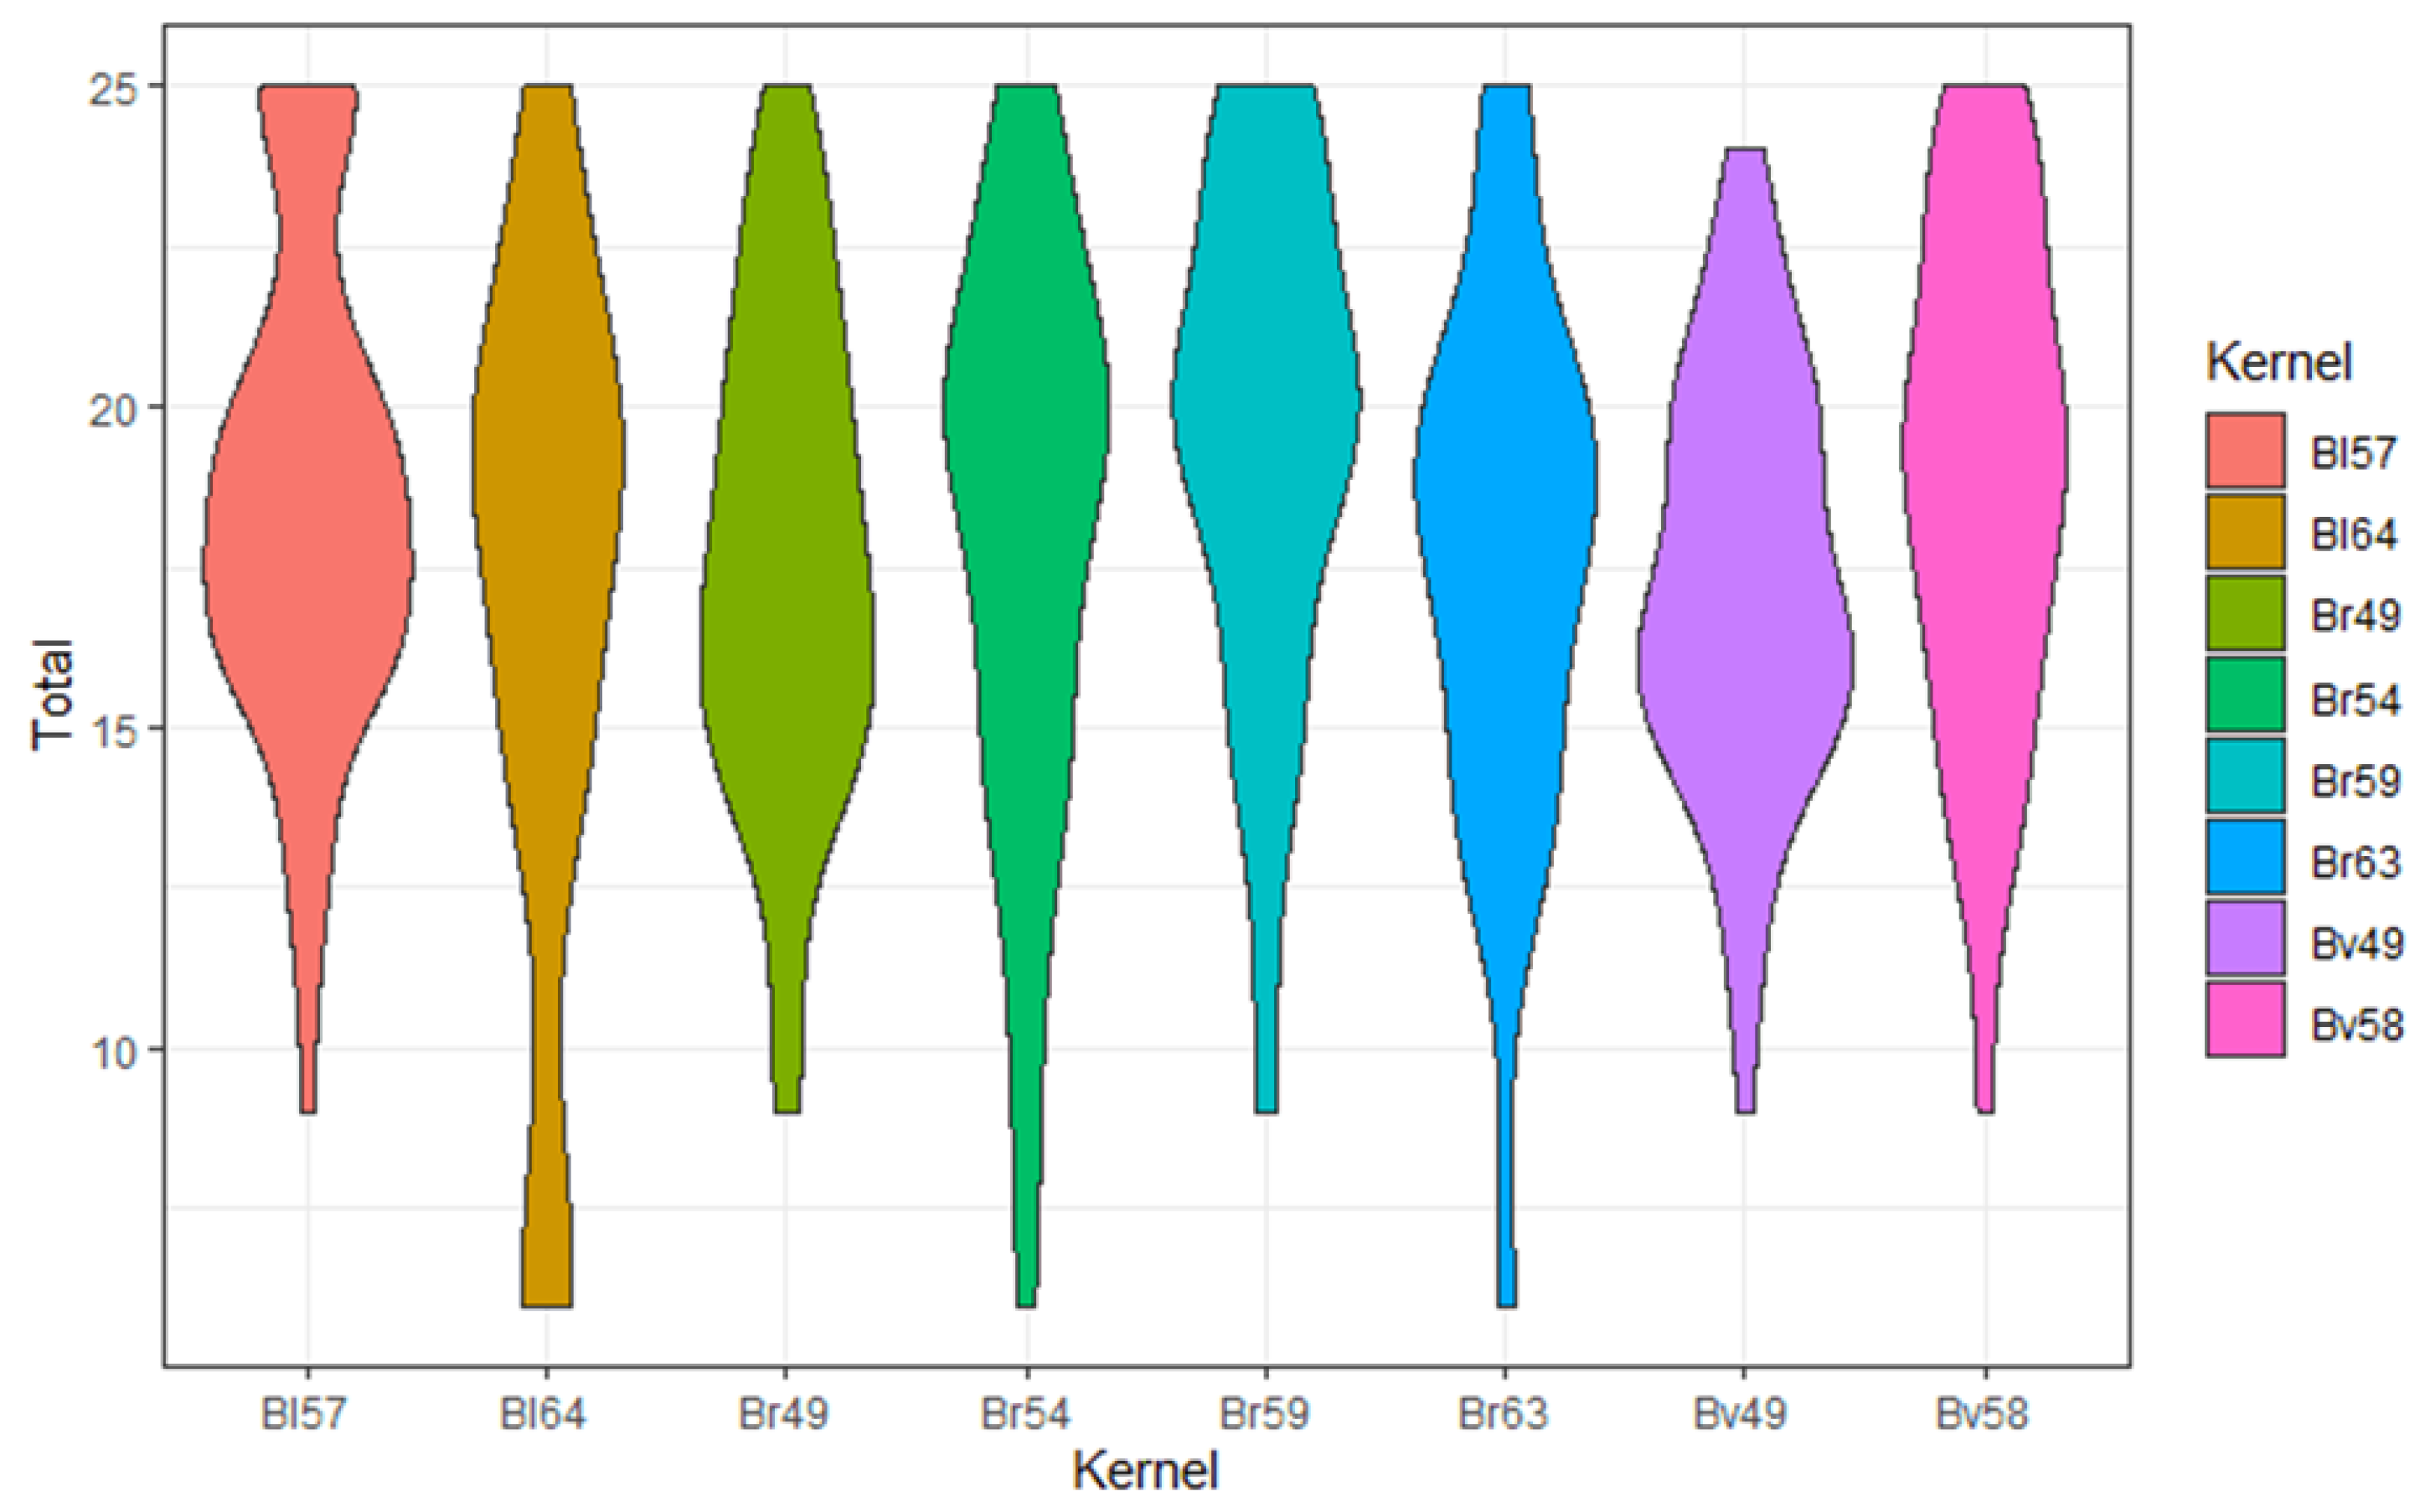

3.2. Comparison of Different Kernels

3.3. Comparison of Different Matrices

| Bl57 | Bl64 | Br49 | Br54 | Br59 | Br63 | Bv49 | Bv58 | ||

|---|---|---|---|---|---|---|---|---|---|

| Sharpness | mean | 4.08 | 3.67 | 3.52 | 3.63 | 4.00 | 3.62 | 3.25 | 3.60 |

| sd | 0.87 | 1.40 | 1.03 | 1.17 | 0.96 | 1.09 | 0.86 | 1.05 | |

| n | 60 | 24 | 60 | 56 | 60 | 60 | 60 | 60 | |

| Noise | mean | 3.18 | 2.67 | 3.52 | 3.43 | 3.43 | 3.02 | 3.58 | 3.55 |

| sd | 1 | 1.13 | 1 | 1.09 | 0.95 | 1.03 | 0.98 | 0.96 | |

| n | 60 | 24 | 60 | 56 | 60 | 60 | 60 | 60 | |

| DoP | mean | 3.83 | 3.58 | 3.50 | 3.63 | 4.03 | 3.70 | 3.47 | 3.90 |

| sd | 0.83 | 1.06 | 0.89 | 0.89 | 0.96 | 0.91 | 0.70 | 0.88 | |

| n | 60 | 24 | 60 | 56 | 60 | 60 | 60 | 60 | |

| DoB | mean | 3.83 | 3.50 | 3.65 | 3.75 | 4.12 | 3.75 | 3.58 | 4.07 |

| sd | 0.98 | 1.10 | 0.71 | 1.07 | 0.96 | 1.00 | 0.81 | 0.86 | |

| n | 60 | 24 | 60 | 56 | 60 | 60 | 60 | 60 | |

| OII | mean | 3.67 | 3.42 | 3.53 | 3.55 | 3.90 | 3.50 | 3.38 | 3.82 |

| sd | 0.82 | 1.18 | 0.83 | 1.03 | 0.84 | 0.89 | 0.74 | 0.81 | |

| n | 60 | 24 | 60 | 56 | 60 | 60 | 60 | 60 | |

| Total | mean | 18.60 | 16.83 | 17.72 | 17.98 | 19.48 | 17.58 | 17.27 | 18.93 |

| sd | 3.77 | 5.53 | 3.77 | 4.64 | 3.99 | 4.20 | 3.23 | 3.91 | |

| n | 60 | 24 | 60 | 56 | 60 | 60 | 60 | 60 |